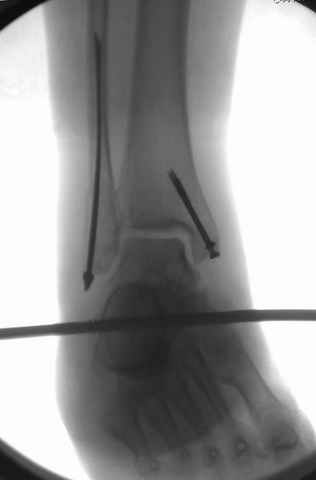

Я вот все в толк не возьму смысл отдельной фиксации малоберцовой кости пластинкой, если все равно будет аппарат с фиксацией стопы, т.е. возможностью провести спицы в пятку, таран, наружную лодыжку и еще черт-те куда. Остеосинтез пластинкой выглядит логичным в случае, когда наружная фиксация планируется как временная. Но тут-то аппарат будет окончательным фиксатором.

Еще, кстати, о фиксации лодыжки, если уж непременно хочется ее отдельно стабилизировать - при таком характере перелома замечательно должен сработать предложенный проф. Лазаревым с соратниками способ фиксации напряженной V-образной спицей. Опять же, открытая репозиция не нужна, мы делаем непрямую репозицию именно аппаратом. В приложении пример, там перелом малоберцовой куда менее поперечный, чем в данном случае, но все равно получилось закрыто без пластинки.

I can't realize why plate fibula separately if anyway external fixator including the foot is planned, i.e. one may insert wires to the talus, calcaneus, lateral malleolus and anywhere else. Plating looks reasonable if only temporary ex-fix is planned, but in the case it will be definitive.

A propos fibular fixation if one is eager to stabilize it separately. In the fracture pattern a way of closed fixation by V-shaped stressed wire (advanced by colleagues from Moscow, prof. Lazarev A.F. et al.) must be excellent. We use indirect closed reduction by the external fixator. Example attached, that fibular fracture is even more suitable for plating but the wire did the job.

I didn't perform stress tests, at least it prevents fibula against secondary displacement. Stressed 2 mm double wire is not so weak.

I used it only in two fibular cases recently. Colleagues from Moscow use the wires mostly for proximal humerus and even femoral neck.